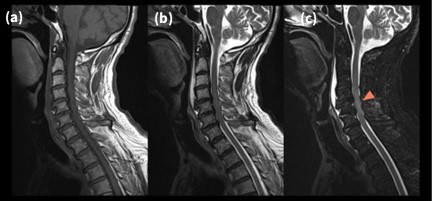

7-2. 頚椎

Fig.7-2に頚椎T2WI の画像を示す。頚椎はCSFのフローやトランケーションを生じやすく、脊髄内に偽病変(アーチファクト)を生じてしまうことを経験する9)。PROPELLER MBを使用することでCSFのフローアーチファクトを抑制(分散)しつつ、ARDLを併用することでトランケーションを低減することができる。また、AIR™ Reconによるノイズレベルに応じた受信チャンネル毎の重みづけ再構成をすることにより、PROPELLER MB独自のアーチファクトも抑制している。本症例は頸髄損傷であるが、上記のテクニックを用いることで迷うことなく所見を指摘することができる。

VoyagerMR30_ube13.jpg

Fig.7-2 頚髄損傷におけるPROPELLERとARDLを併用した 頚椎(髄)画像

(a) T1 FSE (b) T2 FSE (c) T2 STIR FSE